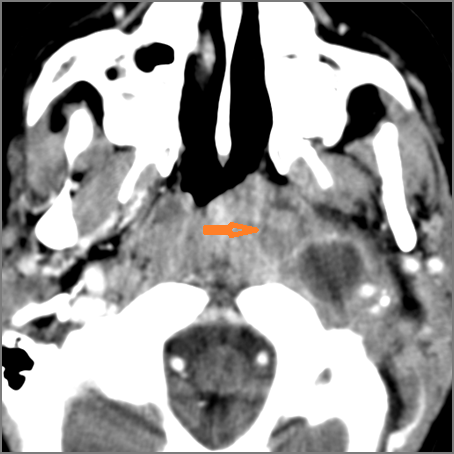

9 month old male presenting to the emergency room with poor feeding, fever, respiratory distress and possible retropharyngeal abscess or suppurative retropharyngeal adenitis.Exam

There is reactive retropharyngeal lymphadenopathy. |

Yes | NA |

There is suppurative retropharyngeal lymphadenopathy. |

If there is suppurative retropharyngeal adenopathy what is the maximum short axis dimension of the largest suppurative node. Measurement |

< 2cm | NA |

There is edema/abscess within the adjacent parapharyngeal and retropharyngeal spaces. |

Pharyngitis with suppurative retropharyngeal adenitis.